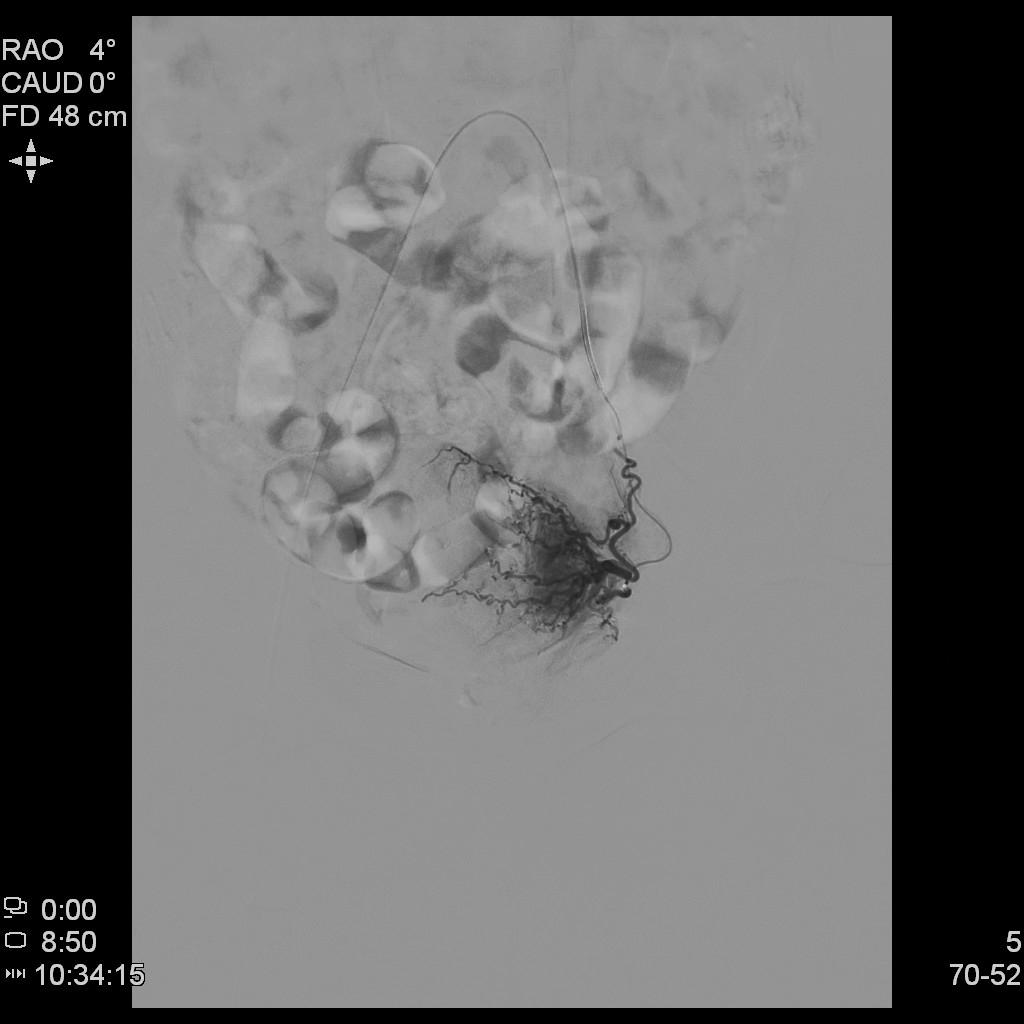

例3

中年患者,发现“子宫腺肌症”10年余,近5年痛经、月经量增多等症状明显加重,导致贫血,严重影响生活质量。

• 术前彩超、磁共振检查显示子宫明显增大,子宫前壁可见弥漫型子宫腺肌症病灶,合并粘膜下、肌壁间子宫肌瘤。

• 经左桡动脉穿刺置管,DSA下行双侧子宫动脉栓塞治疗。

腹主动脉造影

左侧子宫造影